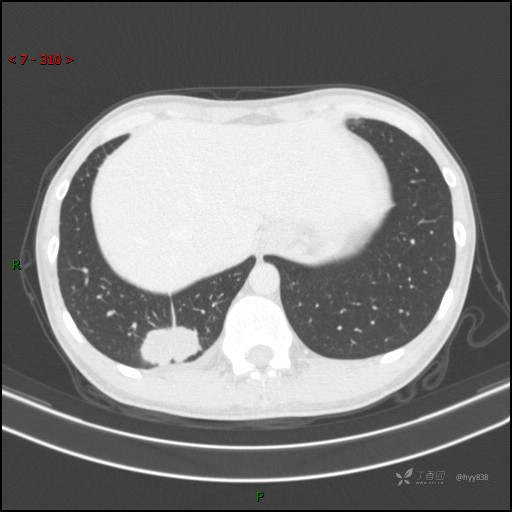

胸部CT平扫